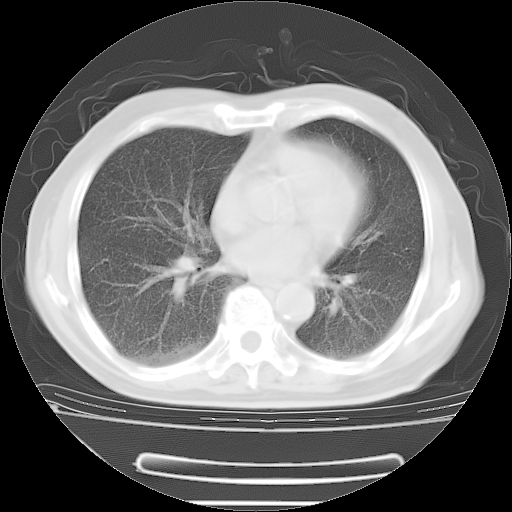

胸腹部CT,诊断意见:左上肺叶钙化灶、左侧胸膜局限性增厚并钙化、胆囊炎。描述部分肺组织呈磨玻璃样改变。